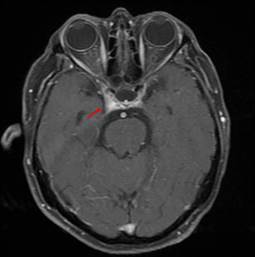

Durante su hospitalización fue valorada nuevamente por el servicio de neurología. Presentaba al examen físico facies dolorosa, hiporexia, cefalea hemicraneal derecha opresivapulsátil, EVA 7/10, fotofobia -que la condicionaba a llevar antifaz-, parálisis incompleta del tercer par craneal derecho sin afectación pupilar, parálisis del cuarto par craneal derecho, así como diplopía que mejoró con la maniobra de Bielschowsky, dolor al movimiento del ojo derecho e hipoestesia en V1 y V2 derechos. También se observó parálisis del sexto nervio derecho (Figura 1). Se realizaron estudios de laboratorio y punción lumbar, que mostraron una alteración única en los niveles de sodio previamente conocidos (Tabla 1). Se solicitó imagen por resonancia magnética (IRM), que evidenció realce del seno cavernoso derecho (Figura 2). Con los datos clínicos obtenidos mediante exploración física y estudios de imagen, así como la ausencia de alteraciones en los estudios de laboratorio, se estableció el diagnóstico de síndrome de Tolosa-Hunt. Se inició tratamiento con dosis altas de corticoides (dexametasona, vía intravenosa, 8 miligramos cada 8 horas), con mejoría de la sintomatología descrita previamente, siendo dada de alta con prednisona en esquema de reducción de dosis. La paciente tuvo una última consulta el 28 de junio de 2021, en la que se observó una mejoría de sus síntomas, y no se registró déficit de movimientos extraoculares (Figura 3).

Figura 2 Imagen por resonancia magnética. Vista axial potenciada en T1. Se nota realce del seno cavernoso derecho (flecha roja)